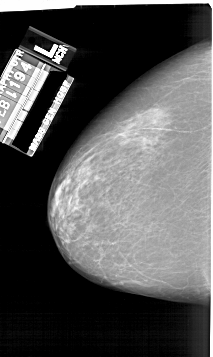

A_1925_1.LEFT_MLO

LEFT_MLO LINES 6406 PIXELS_PER_LINE 3586 BITS_PER_PIXEL 12 RESOLUTION 43.5 NON_OVERLAY